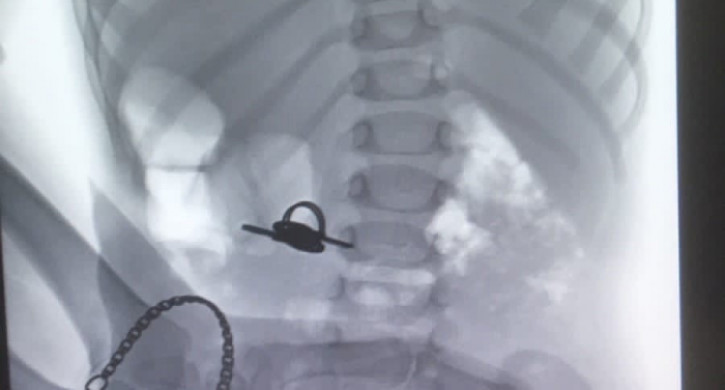

В ЧОДКБ из желудка малыша извлекли связку ключей

В ЧОДКБ из желудка ребенка извлекли ключи, передает корреспондент Агентства новостей «Доступ» со ссылкой на больницу.

Сообщается, что полуторагодовалый малыш проглотил связку ключей. Врачи-эндоскописты извлекли инородный предмет из желудка ребенка.